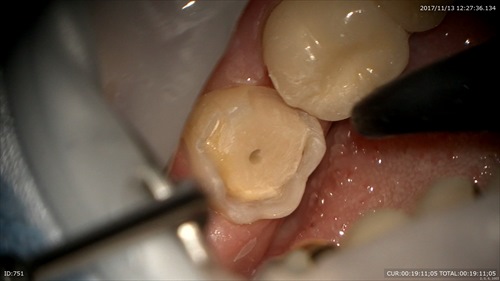

4:土台を作り精密な型取り

次回詰め物が入ります。楽しみですねー。